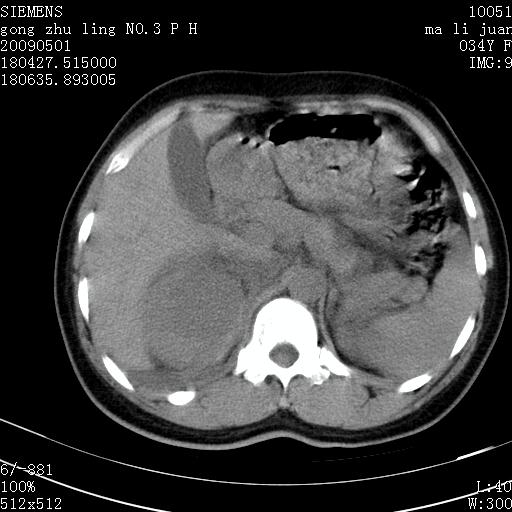

标题: CT19733:右肾碎裂

青年女性,骑摩托车摔伤。

支持 右肾破裂伴肾包膜下及肾周血肿。

右肾破裂并右侧腹膜后间隙出血。

右肾破裂伴肾包膜下及肾周血肿。

支持 右肾破裂伴肾包膜下及肾周血肿